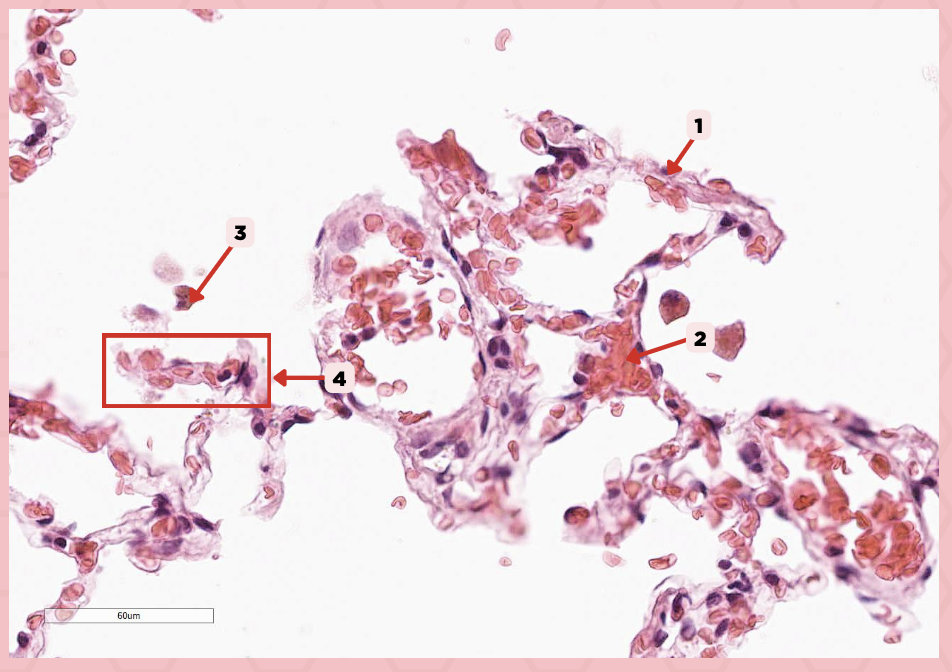

Interalveolar septum

Identify the structure labeled as 1.

Type I alveolar cell

Identify the structure labeled as 2.

Type II alveolar cell

Identify the structure labeled as 3.

Pulmonary Alveolar Macrophages (Dust Cells)

Identify the structure labeled as 4.

Pulmonary Alveolar Macrophages (Dust Cells)

What are the most numerous cells inside the alveoli?

Pneumocyte Type I

Which of the following labeled structures covers 95% of the alveolar surface?

Type I alveolar cell

Identify the structure labeled as 1.

Type II alveolar cell

Identify the structure labeled as 2.

Pulmonary Alveolar Macrophages (Dust Cells)

Identify the structure labeled as 3.

Endothelial Cells

Identify the structure labeled as 4.